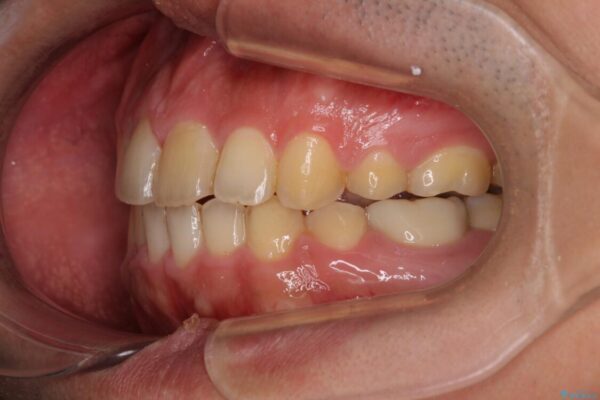

治療前

• 後戻りでデコボコの前歯 インビザライン矯正治療 治療前画像